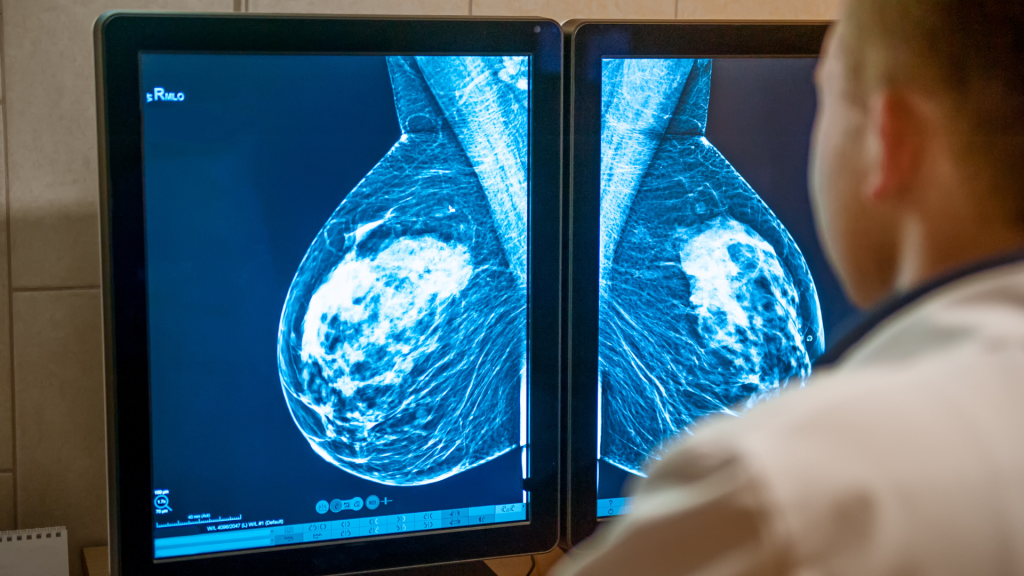

سرطان پستان زمانی رخ می دهد که سلول های غیرطبیعی در بافت پستان شروع به رشد و تکثیر کنترل نشده می کنند. این بیماری می تواند به صورت توده، تغییرات پوستی یا ترشحات غیرطبیعی بروز کند و در صورت تشخیص زودهنگام به خوبی قابل درمان است.

سرطان پستان یکی از رایجترین انواع سرطان در زنان است و با رشد غیرطبیعی سلولها در بافت پستان مشخص میشود. این بیماری میتواند در یک یا هر ...